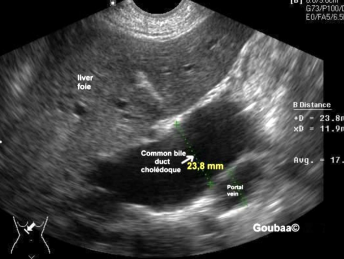

Biliary/ductal dilatations

When sweeping through the liver, if you see dilated structures, investigate the surrounding organs and make sure to confirm whether it’s a duct or a vessel (color, turn on it)

enlargement/neoplasia of pancreas head → stenosis or complete obstruction of the distal common bile duct

(when there’s a mass or inflammation in panc head, it compresses or obstructs CBD so bile can’t drain and bilirubin rises)

“head hits the hepatic highway”